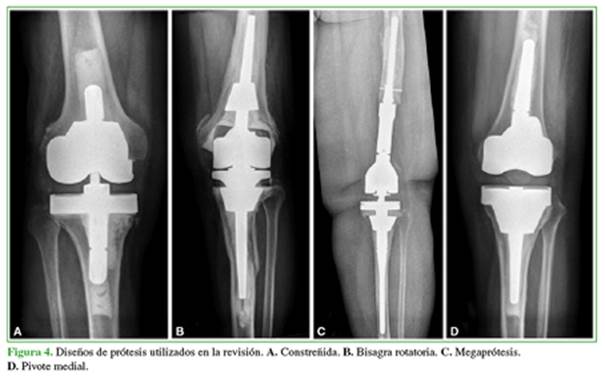

En 10 casos, se usó una combinación de conos femorales y tibiales, y en tres casos, se combinaron conos metafisarios y diafisarios en un mismo paciente. En cuanto a los diseños de la prótesis para la revisión (Figura 4), más de la mitad fueron prótesis constreñidas (n = 20; 57,1%), el 20% fueron bisagras rotatorias (n = 7); el 20%, megaprótesis (n = 7) y una de pivote medial (2,8%). En dos casos, se usó, además, un injerto óseo impactado a nivel del fémur y, en cinco, se realizó una reconstrucción del aparato extensor (3 con aloinjerto y 2 con malla).